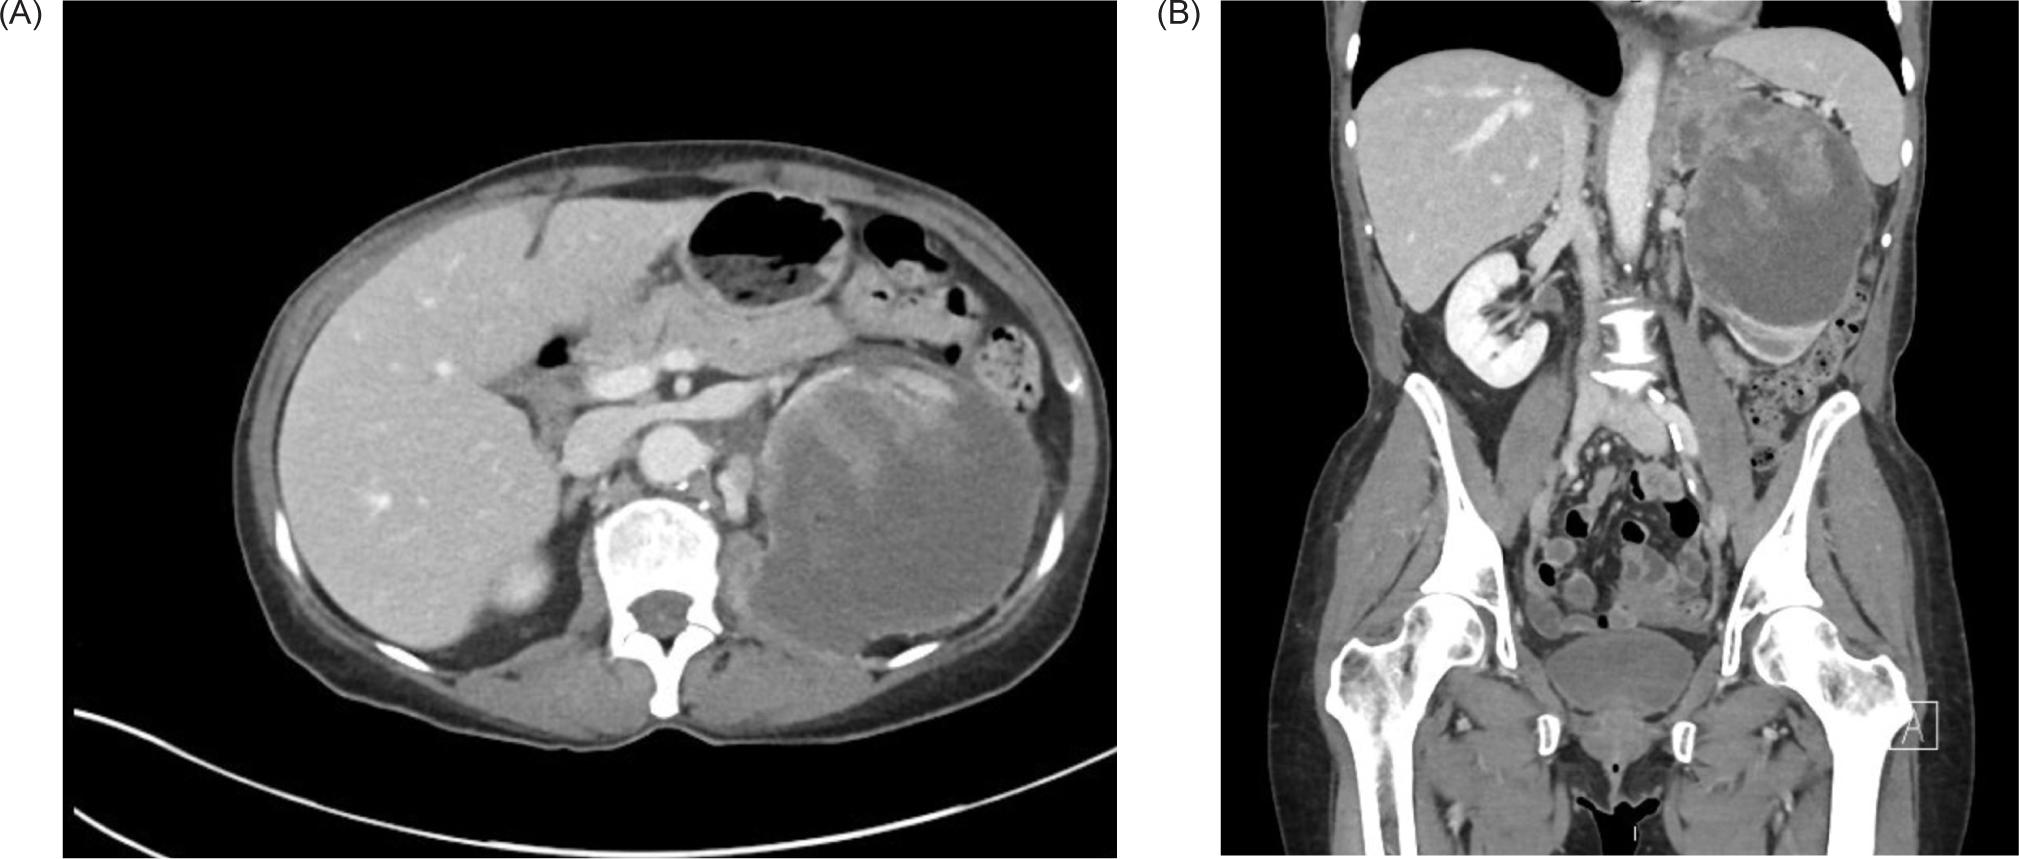

A 59-year-old female smoker with history of hypertension and hyperlipidemia who was screened for lung cancer with yearly low-dose CT scans was incidentally found to have a large left renal mass. Further evaluation via CT revealed a complex enhancing renal mass measuring 9.2.2 × 9.3 × 12.4 cm with extension into the left psoas muscle and abutting the pancreatic tail, spleen, and stomach (Figure 1). The patient underwent excision of a soft tissue mass, and surgical pathology was consistent with sarcoma. PET-CT scan revealed multiple avid lesions including lung nodules of up to 1.5 cm, a left adrenal mass, retroperitoneal adenopathy, and soft tissue metastases in the pelvic muscles as well as a lesion near the right atrium (Figure 2). An echocardiogram was performed in order to further evaluate the cardiac finding on the PET-CT scan, which revealed a 3.5 × 3.4 cm mass attached to the right atrial free wall, which was thought to represent a large thrombus or cardiac tumor, as well as a 0.75 cm mass noted on the atrial aspect of the IVC-RA junction likely representing the thrombus. Left ventricle ejection fraction was normal at 65%. The patient was instructed by her cardiologist to present to the Emergency Department for further evaluation given these findings. On presentation, the patient reported intermittent left flank pain, EKG was normal sinus rhythm with no acute ST changes, and CTA scan revealed likely invasion of perivascular nodules in the right upper lobe into subsegmental pulmonary arterial branches with associated pulmonary emboli within the distal subsegmental and more distal branches. The following day, cardiac MRI confirmed an intra-cardiac tumor occupying the entire right atrium with extension through the myocardium into the epicardial space and through the tricuspid valve into the right ventricle (Figure 3). MRI brain revealed three lesions consistent with metastatic disease. Renal biopsy was consistent with clear cell RCC with sarcomatoid features (Figure 4). Immunohistochemical studies were positive for desmin, PAX8, and myogenin, and negative for CK7. Patient was identified as poor risk per International Metastatic RCC Database Consortium (IMDC), with a median survival of 7.8 months. The patient received Ipilimumab and Nivolumab for one cycle, followed by Nivolumab only due to complication of diarrhea requiring steroid therapy. After three months of therapy that included three cycles of total therapy, she was noted to have partial response per Response Evaluation Criteria in Solid Tumors (RECIST) criteria. The patient will be continued on Nivolumab. The patient was also treated with gamma knife radiosurgery for her brain metastases.

Figure 2: PET-CT of the chest, abdomen, and pelvis. (A) Axial and (B) coronal views demonstrating a FDG uptake of the right atrium suggestive of a cardiac metastasis. There are also FDG avid pulmonary nodules. (C) Axial and (D) coronal views demonstrating a heterogeneously attenuating 9.6 × 8.7 cm left renal mass and accompanying 5.9 × 4.3 FDG avid adrenal mass. There is also a 2.6 × 1.2 cm FDG avid right adrenal metastasis and multiple FDG avid abdominopelvic nodules.